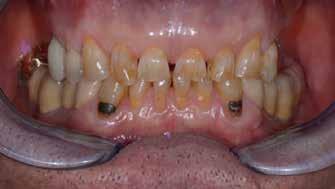

Preoperatív helyzet

Egy fiatal páciens jelentkezett nálunk, akinek eltörött a szabad véggel rendelkező hídja (1. ábra). A hiányzó, első premoláris fog esetén implantációs pótlást javasoltunk. A csontállomány értékeléséhez CBCT-vizsgálatot végeztünk, és az elemzéséhez NNT Viewert (NewTom) használtunk, és copaSKY 4×10 mm-es (bredent medical) implantátumot választottuk a fog pótlásához

1. ábra: Műtét előtti fogászati panorámafelvétel, amelyen a hiányzó felső állcsont jobb első premolárisát és a szabad véggel rendelkező hidat láthatjuk. — 2. ábra: Az implantátum méreteinek megtervezése CBCT-vel. 3. ábra: Bukkális lágyrészdefektus. — 4. ábra: A biológiai szélesség értékelése a vertikális lágyszövetvastagság alapján. 5. ábra: Palatinális „tekercslebeny” – Palatal roll flap. — 6. ábra: Bredent medical copaSKY 4x10 implantátumbeültetés. 7. ábra: Szubkresztális implantátumbeültetés a várható biológiai szélességnek megfelelően.

(2. ábra). A lágyszövetek értékelése Seibert szerinti I. osztályú csontdefektust állapított meg (3. ábra), ezért a beavatkozáskor palatinális „tekercslebenyt” preparáltunk (palatal roll flap), és implantációt végeztünk, hogy kompenzálni tudjuk a bukkális lágyszövet-behúzódást. Megmértük a vertikális lágyszövetvastagságot, és úgy terveztük, hogy a szubkresztális implantátum beültetése összhangban legyen a biológiai szélesség kialakulásával a transzgingivális gyógyulási periódus alatt (4. ábra)